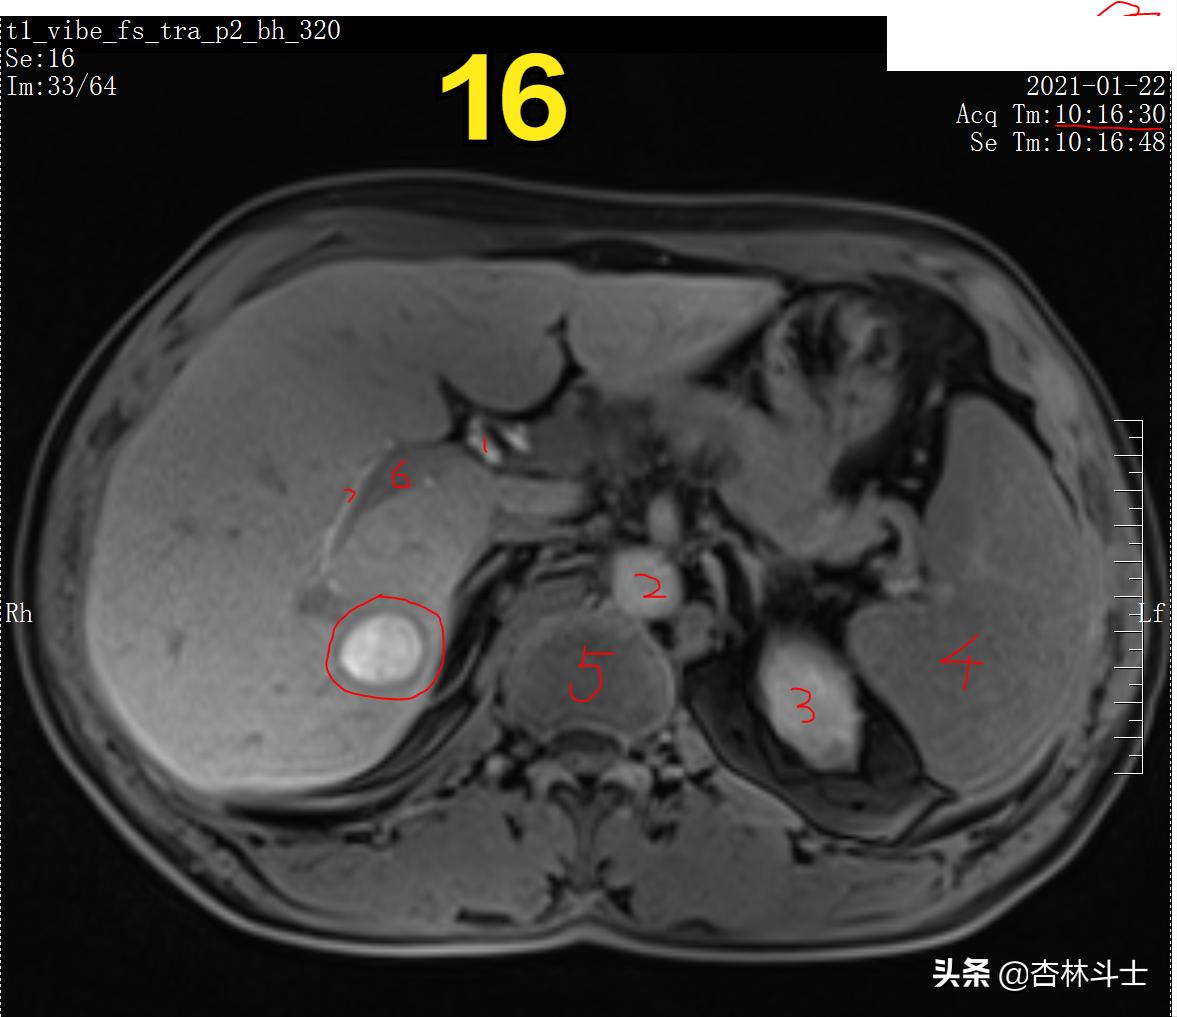

图16 T1加权压脂肝胆特异期

图12-16 持续20余分钟,病灶内仍有特异性对比剂。